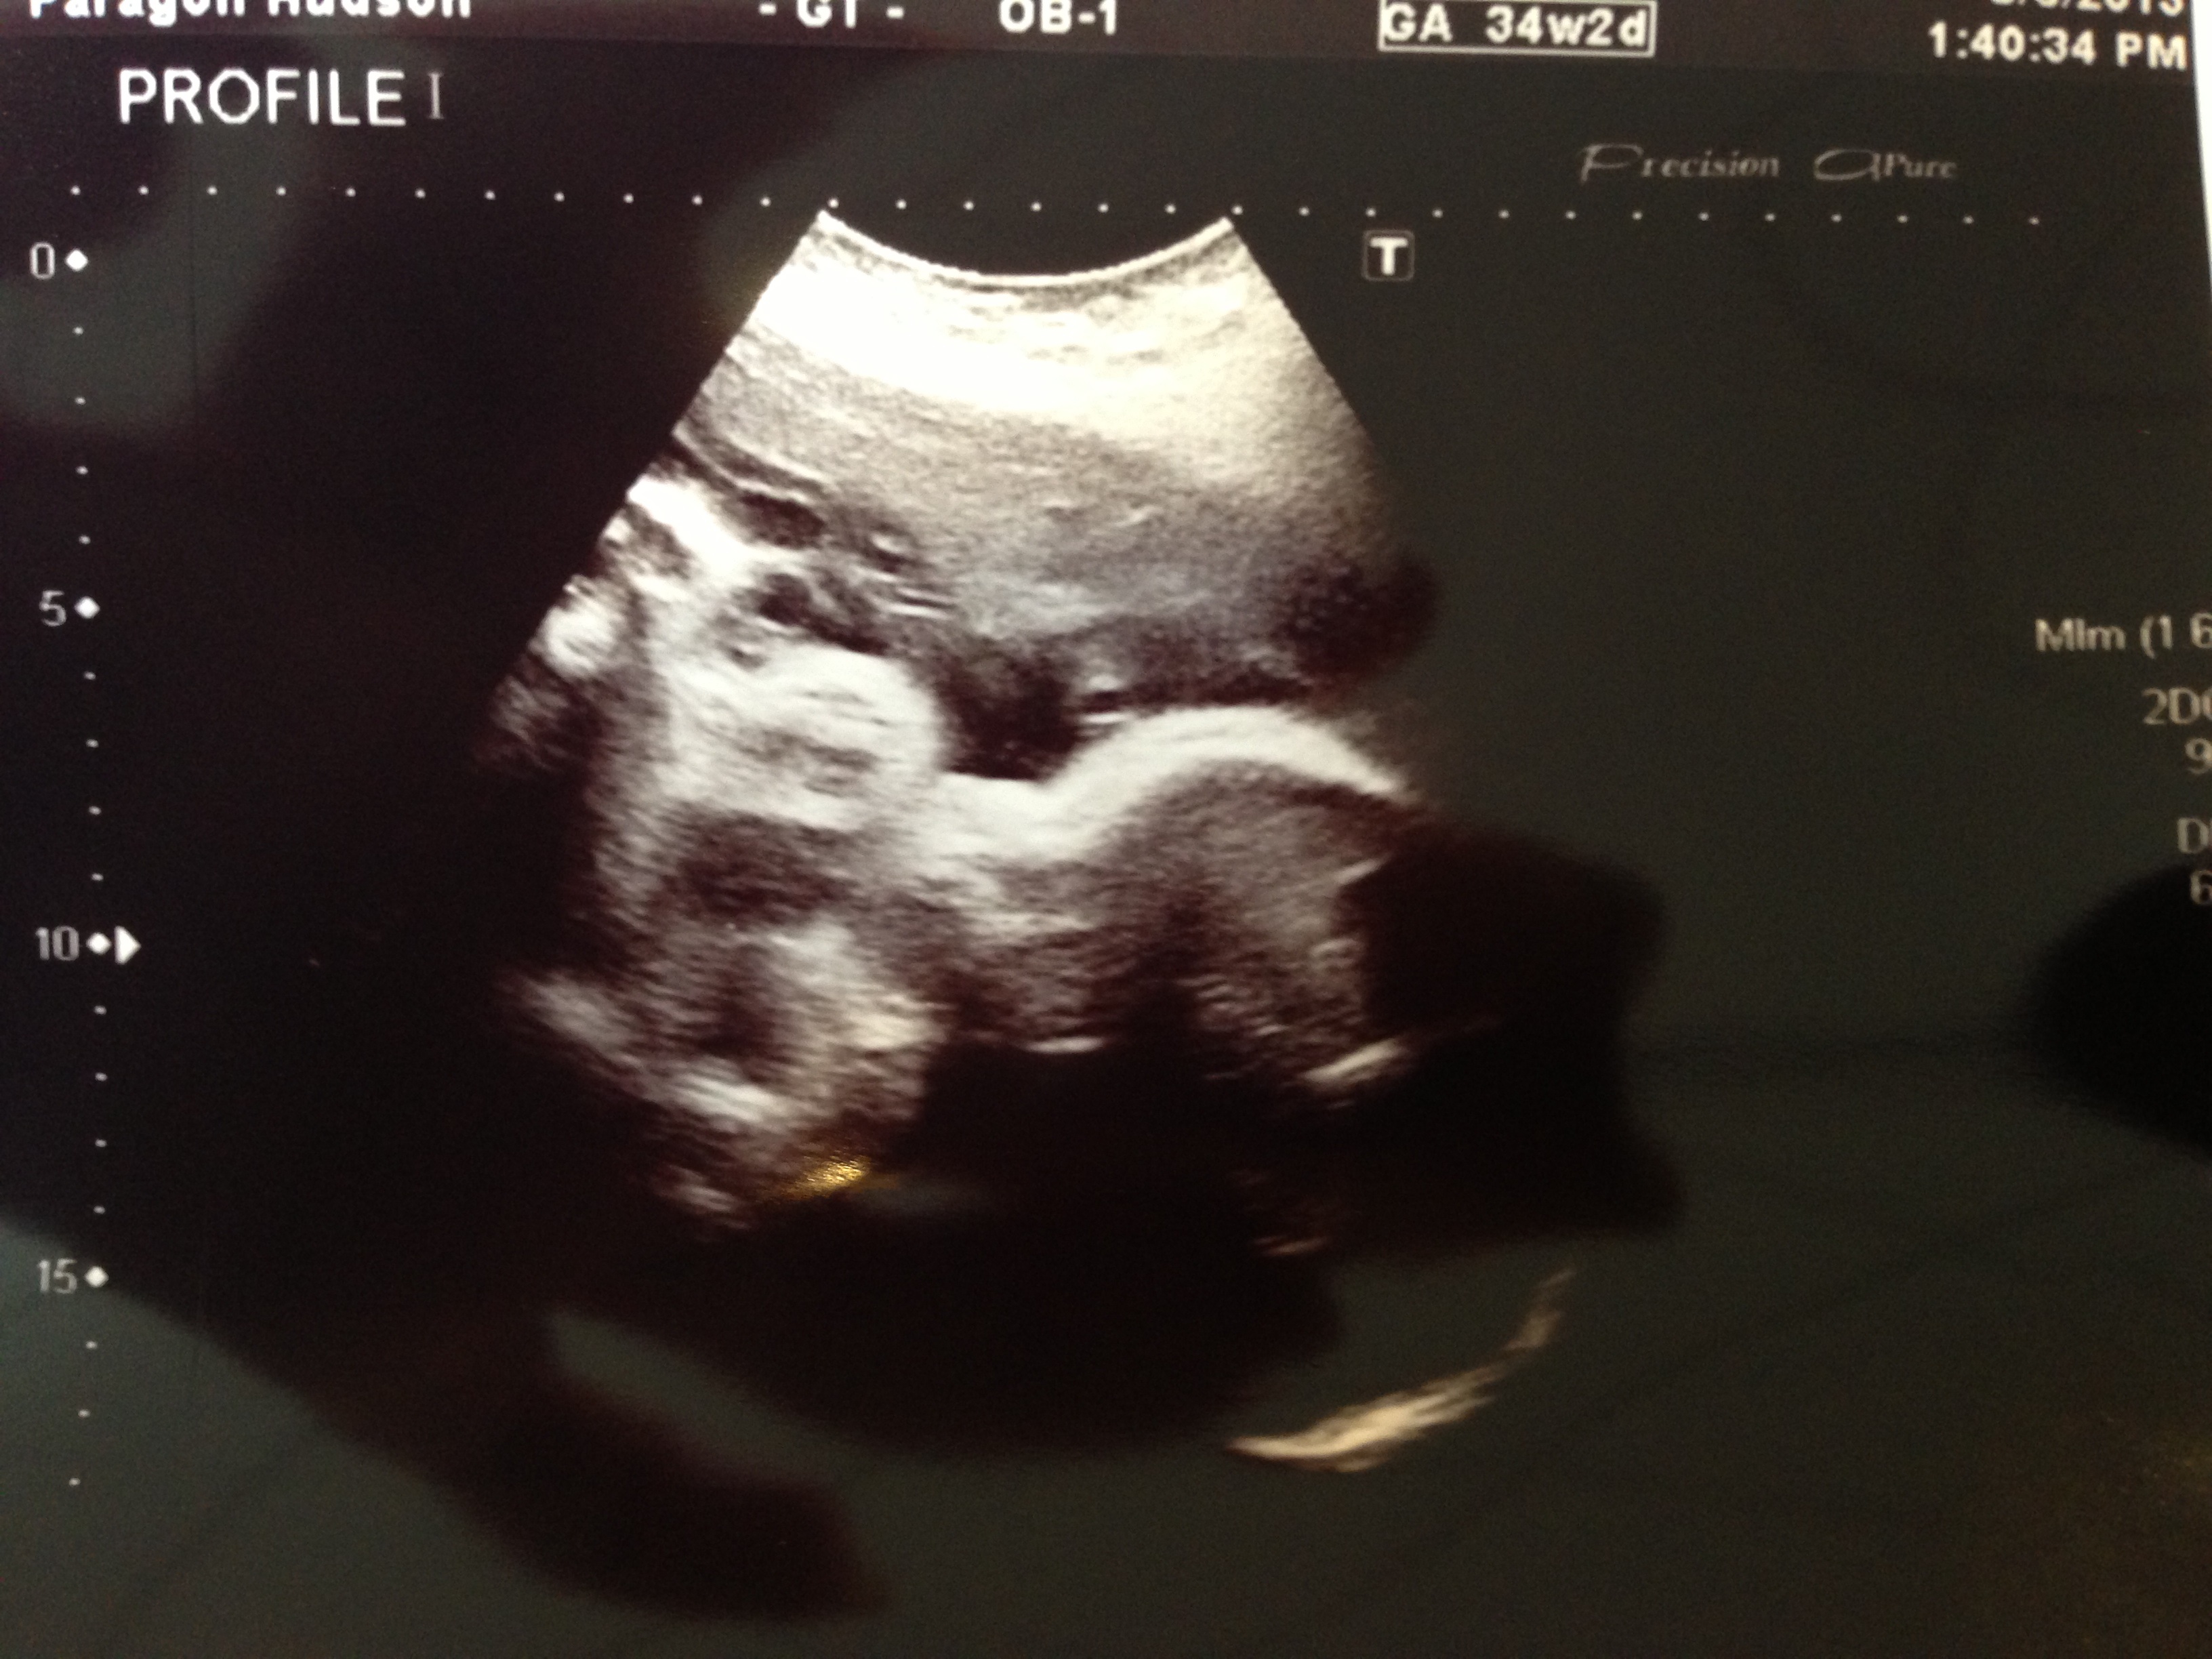

Here's the bump last Saturday and then our most recent growth ultrasound. She's measuring a whopping 6 pounds 11 ounces!